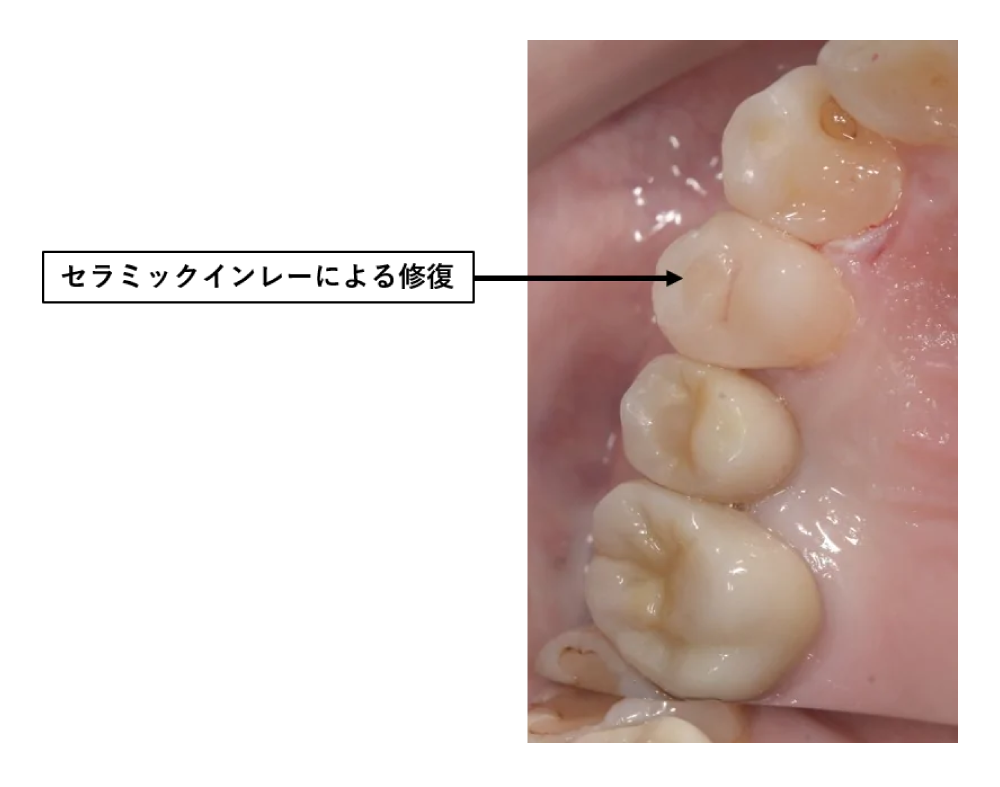

・光学印象によるインプラント欠損補綴治療 ・16光学印象によるセラミッククラウン補綴治療 ・14光学印象によるセラミックインレー修復処置 |

・インプラント 40万円程度 ・セラミッククラウン 10万円程 ・セラミックインレー 4万円程 |